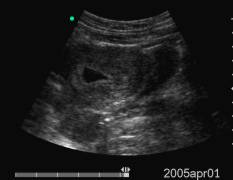

Data inserimento: 15 /07/2005Data esame: 28/06/2005 Strumento: Toshiba 380A Età paziente: F 40 anni Gravidanza alla V settimana di gestazione, documentata per via sovrapubica e per via transvaginale, con evidenza in ambedue le modalità della camera gestazionale. Elaborazione digitale: Andrea Dini